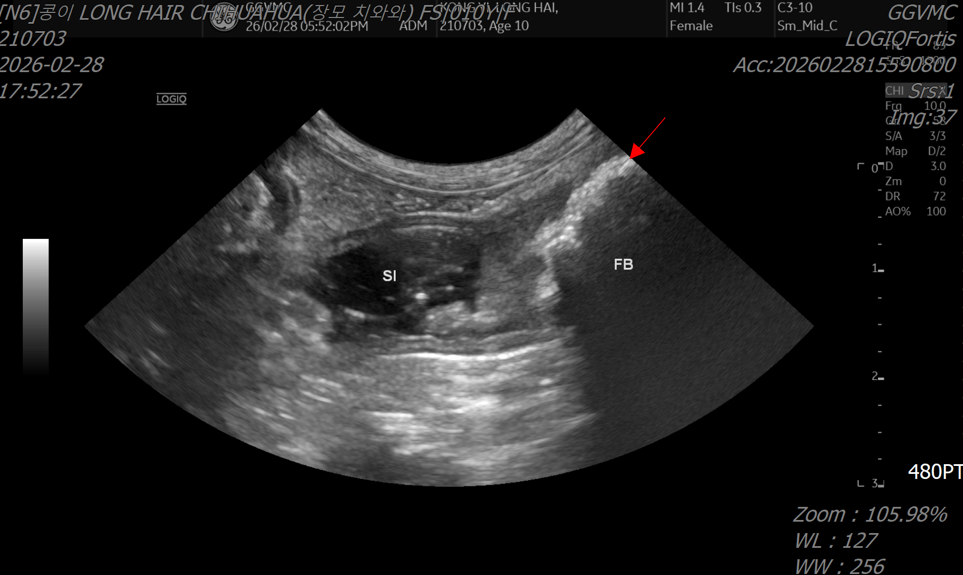

- 초음파 검사에서도 소장 폐색이 의심되는 소견이 확인되었습니다.

초음파 검사: 소장 폐색 의심 소견

<초음파 검사>